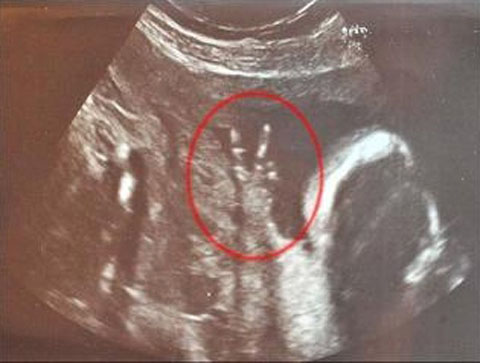

小嬰兒在英國媽媽肚里比出V字勝利手勢(圖)

中新網7月10日電 據臺灣東森新聞報道,即將為人母的英國女子卡羅琳巴恩斯已懷孕23周。最近她去照超聲波,結果發現肚子里的孩子竟然比出結結實實的V字型勝利手勢。

目前35歲,在電視臺擔任分區經理的卡羅琳說:“醫院里的護士笑到不行。在照超聲波的整個過程中,他的手勢都是這個樣子。”